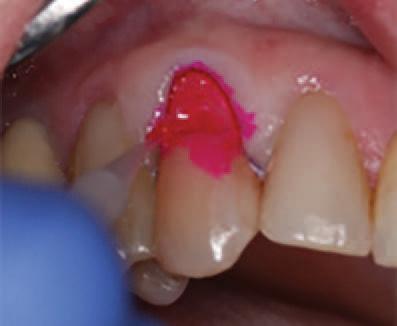

To improve isolation and soft tissue access, a retraction cord was placed before initiating the procedure (Fig. 2). The tooth was evaluated using a caries indicator dye (Kuraray Noritake Dental), helping to identify any remaining infected tissue beneath the dislodged composite (Fig. 3). Decay removal was completed with a diamond bur, and the enamel was bevelled using a starburst pattern to enhance aesthetic blending (Fig. 4). This preparation design was chosen for visual integration rather than bond strength enhancement.

Application of caries indicator dye to identify remaining infected tissue beneath the dislodged composite.